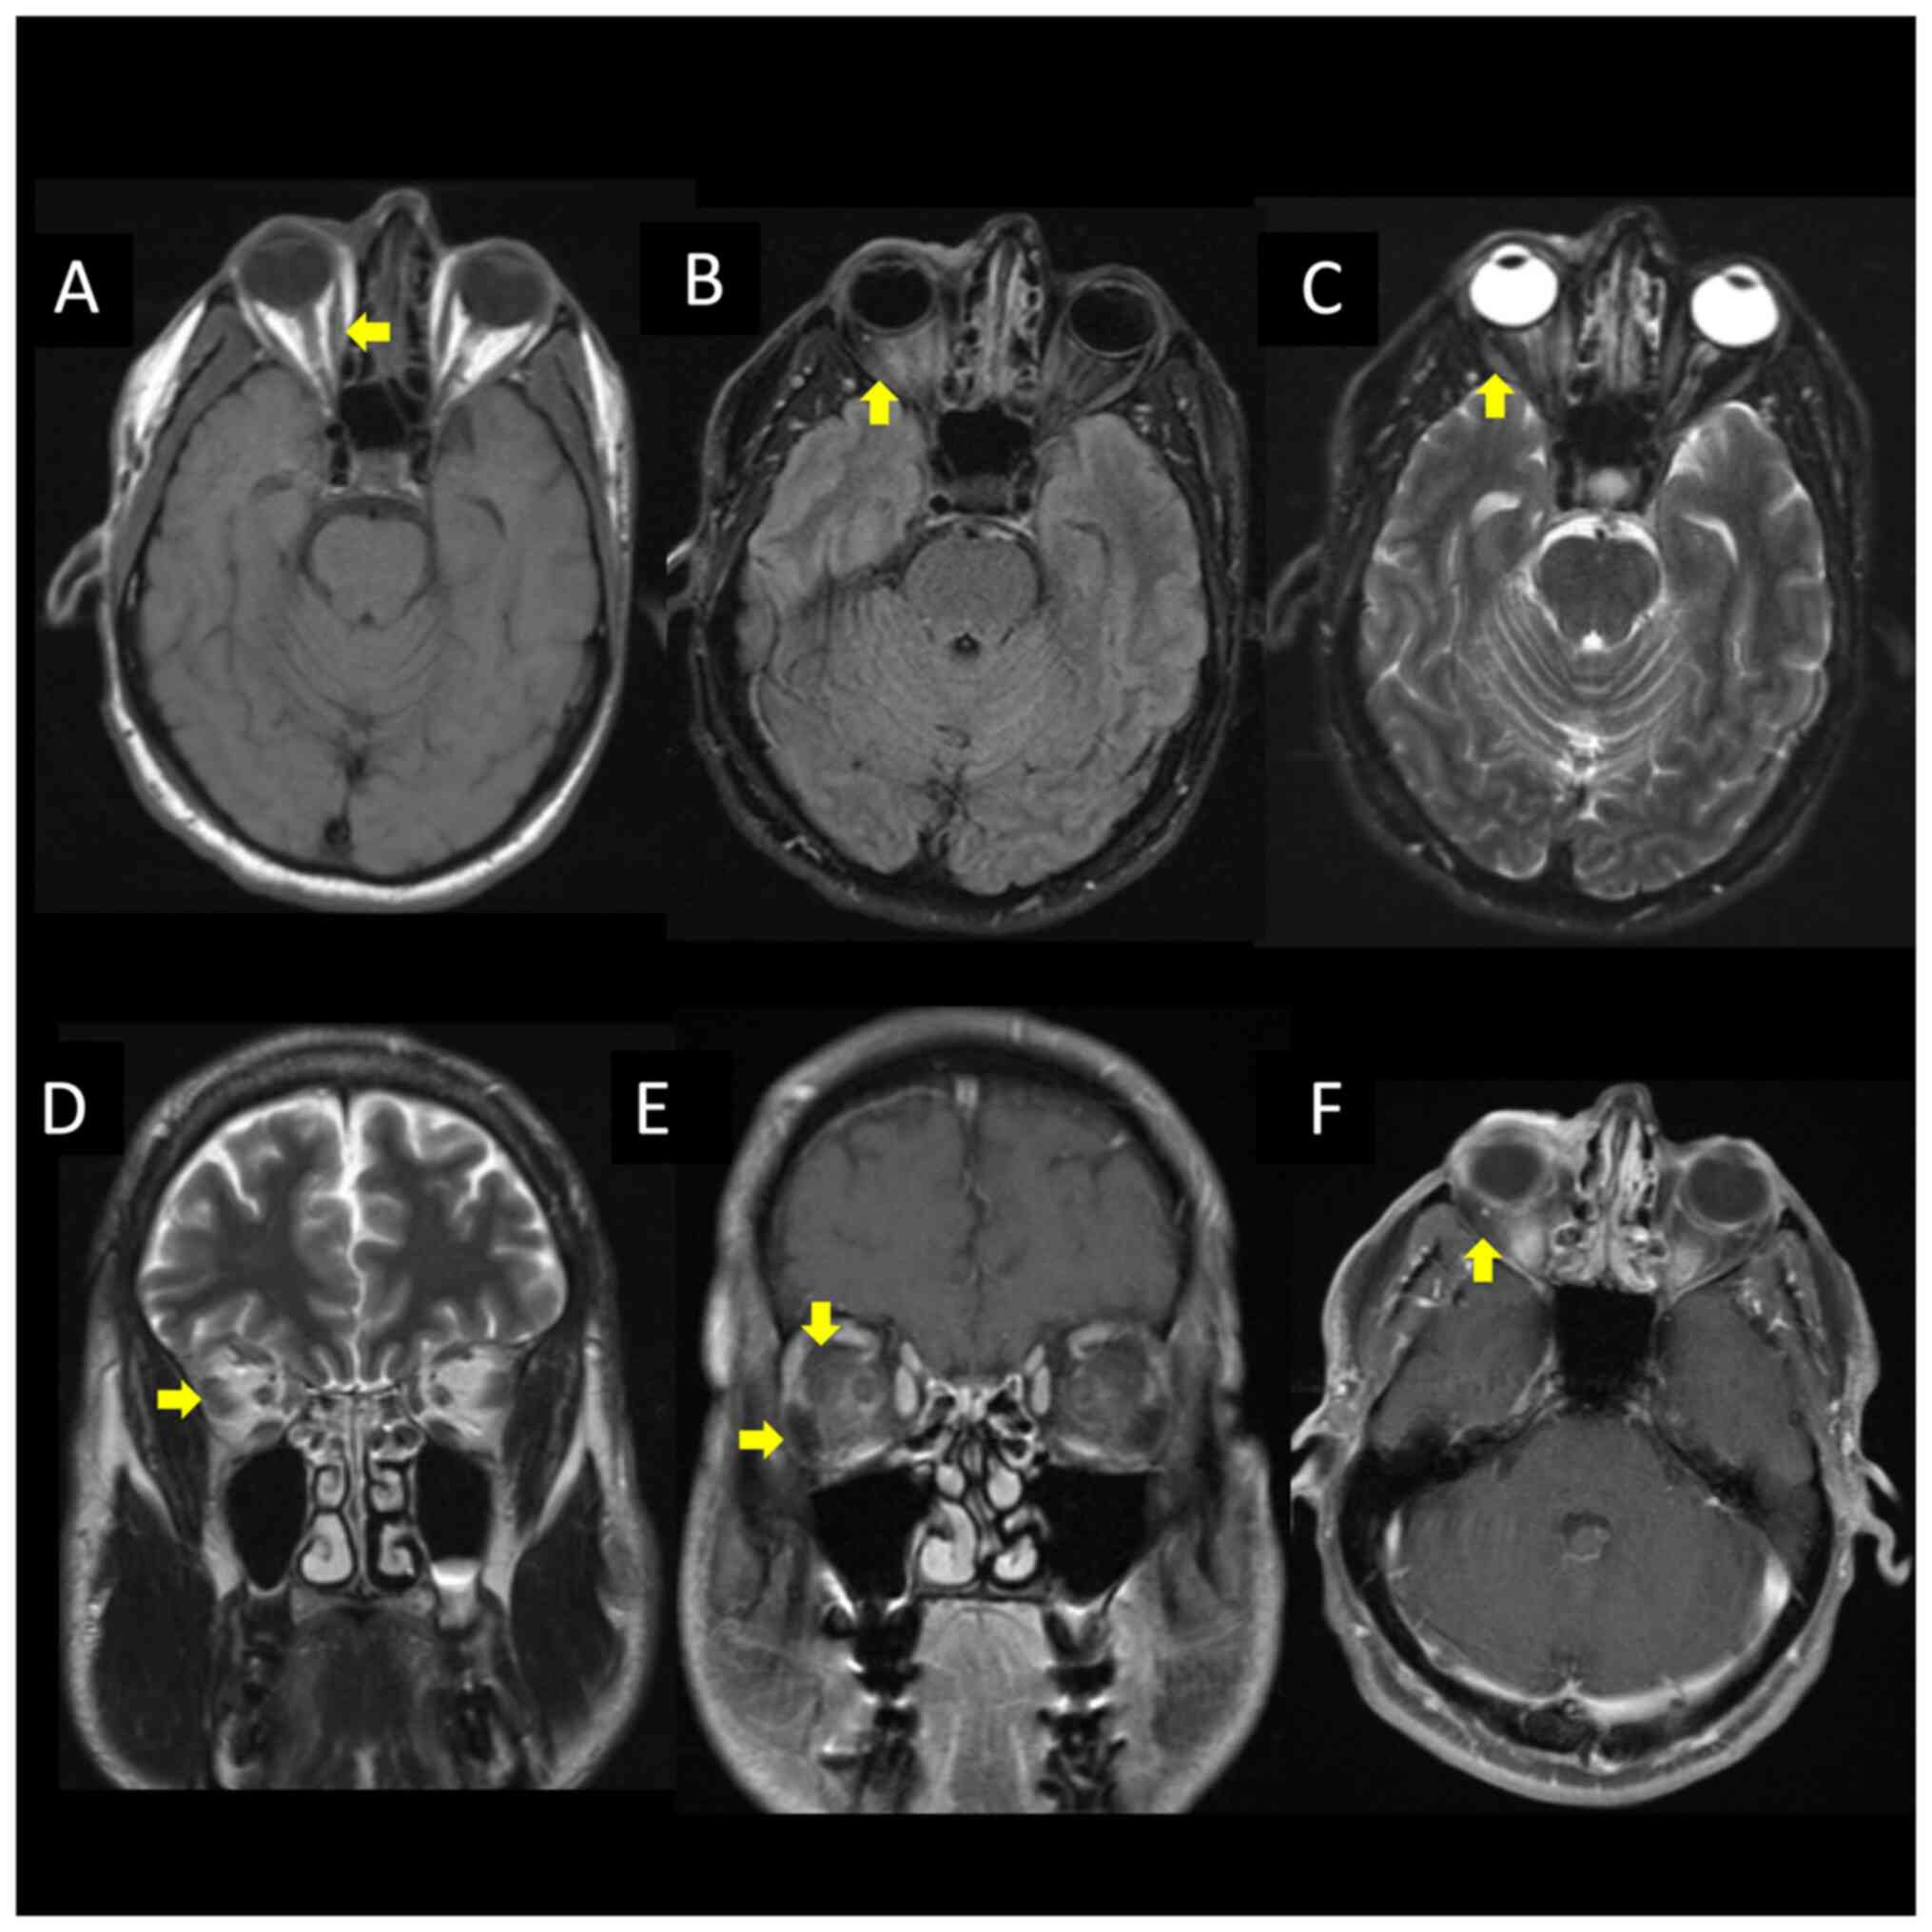

Herpes zoster ophthalmicus presenting with orbital myositis prior to the appearance of vesicular lesions: A case report and mini‑review of the literature

All orbital tissues, including extra‑ocular muscles, can be affected by the varicella‑zoster virus (VZV). However, only a minority of all individuals with herpes zoster infections present with herpes zoster ophthalmicus. The present study reports the case of a middle‑aged male patient presenting with an acute intractable right‑sided headache. His neurological examination yielded normal results. The analysis of cerebrospinal fluid by biochemistry and cultural analysis yielded normal results; however, the analysis of this fluid using polymerase chain reaction yielded a positive result for VZV. Thus, treatment with acyclovir was commenced. Brain magnetic resonance imaging revealed a bilateral intraorbital intraconal enhancement consistent with myositis. His symptoms evolved into a shock‑like pain over the scalp associated with painful ocular movements. On the 2nd day of admission, he developed new vesicular lesions found on the right‑side cranial nerve V1 dermatome. By the 6th day of admission, he was asymptomatic, and his physical examination revealed the resolution of the dermatologic manifestations of the VZV. The patient was stable for outpatient follow‑up with ophthalmology and was discharged on an oral valacyclovir course for 7 days. To the authors' knowledge, there are four cases reported in the literature of herpes zoster ophthalmicus with orbital myositis prior to the appearance of vesicular lesions. Thus, it is suggested that VZV serology be investigated before a final diagnosis of idiopathic orbital myositis is made.